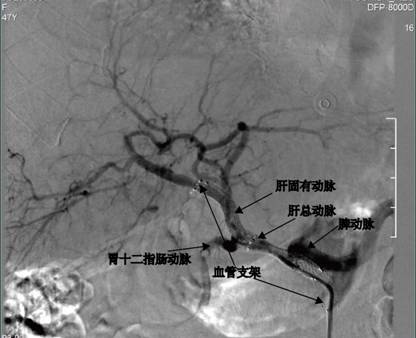

图3腹腔干造影提示肝总动脉夹层动脉瘤形成(膨大部位为假腔)。

图4 导管进入夹层动脉瘤内造影(膨大部位为假腔)。

图5 微导管超选进入肝总动脉真腔(真腔管径细)

图6 支架置入后造影显示,肝总动脉真腔开通,假腔消失。